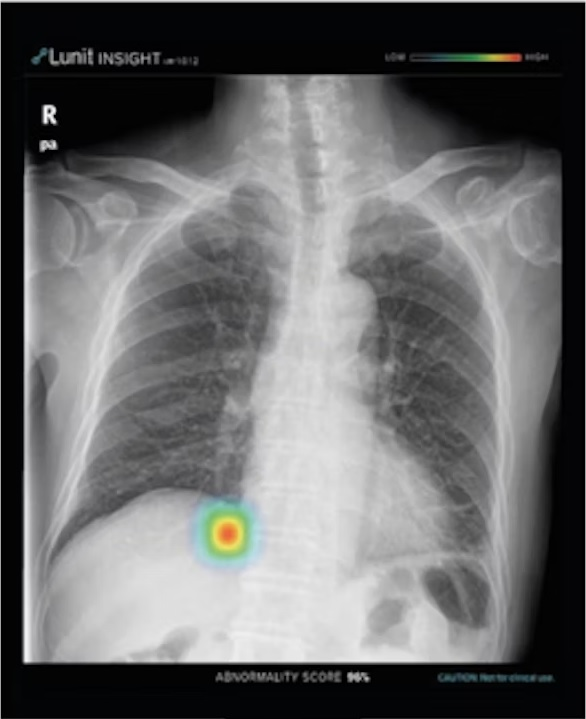

Chest x-ray examples of (A, C) local (feature-based) AI explanations and (B, D) global (prototype-based) AI explanations from a simulated AI tool, ChestAId, presented to physicians in the study. In all examples, the correct diagnostic impression for the radiograph case in question is “right upper lobe pneumonia,” and the corresponding AI advice is correct. The patient clinical information associated with this chest radiograph was “a 63-year-old male presenting to the emergency department with cough.” To better simulate a realistic AI system, explanation specificity was changed according to high (i.e., 80%−94%) or low (i.e., 65%–79%) AI confidence level: bounding boxes in high-confidence local AI explanations (example in A) were more precise than those in low-confidence ones (example in C); high-confidence global AI explanations (example in B) had more classic exemplar images than low-confidence ones (example in D), for which the exemplar images were more subtle.